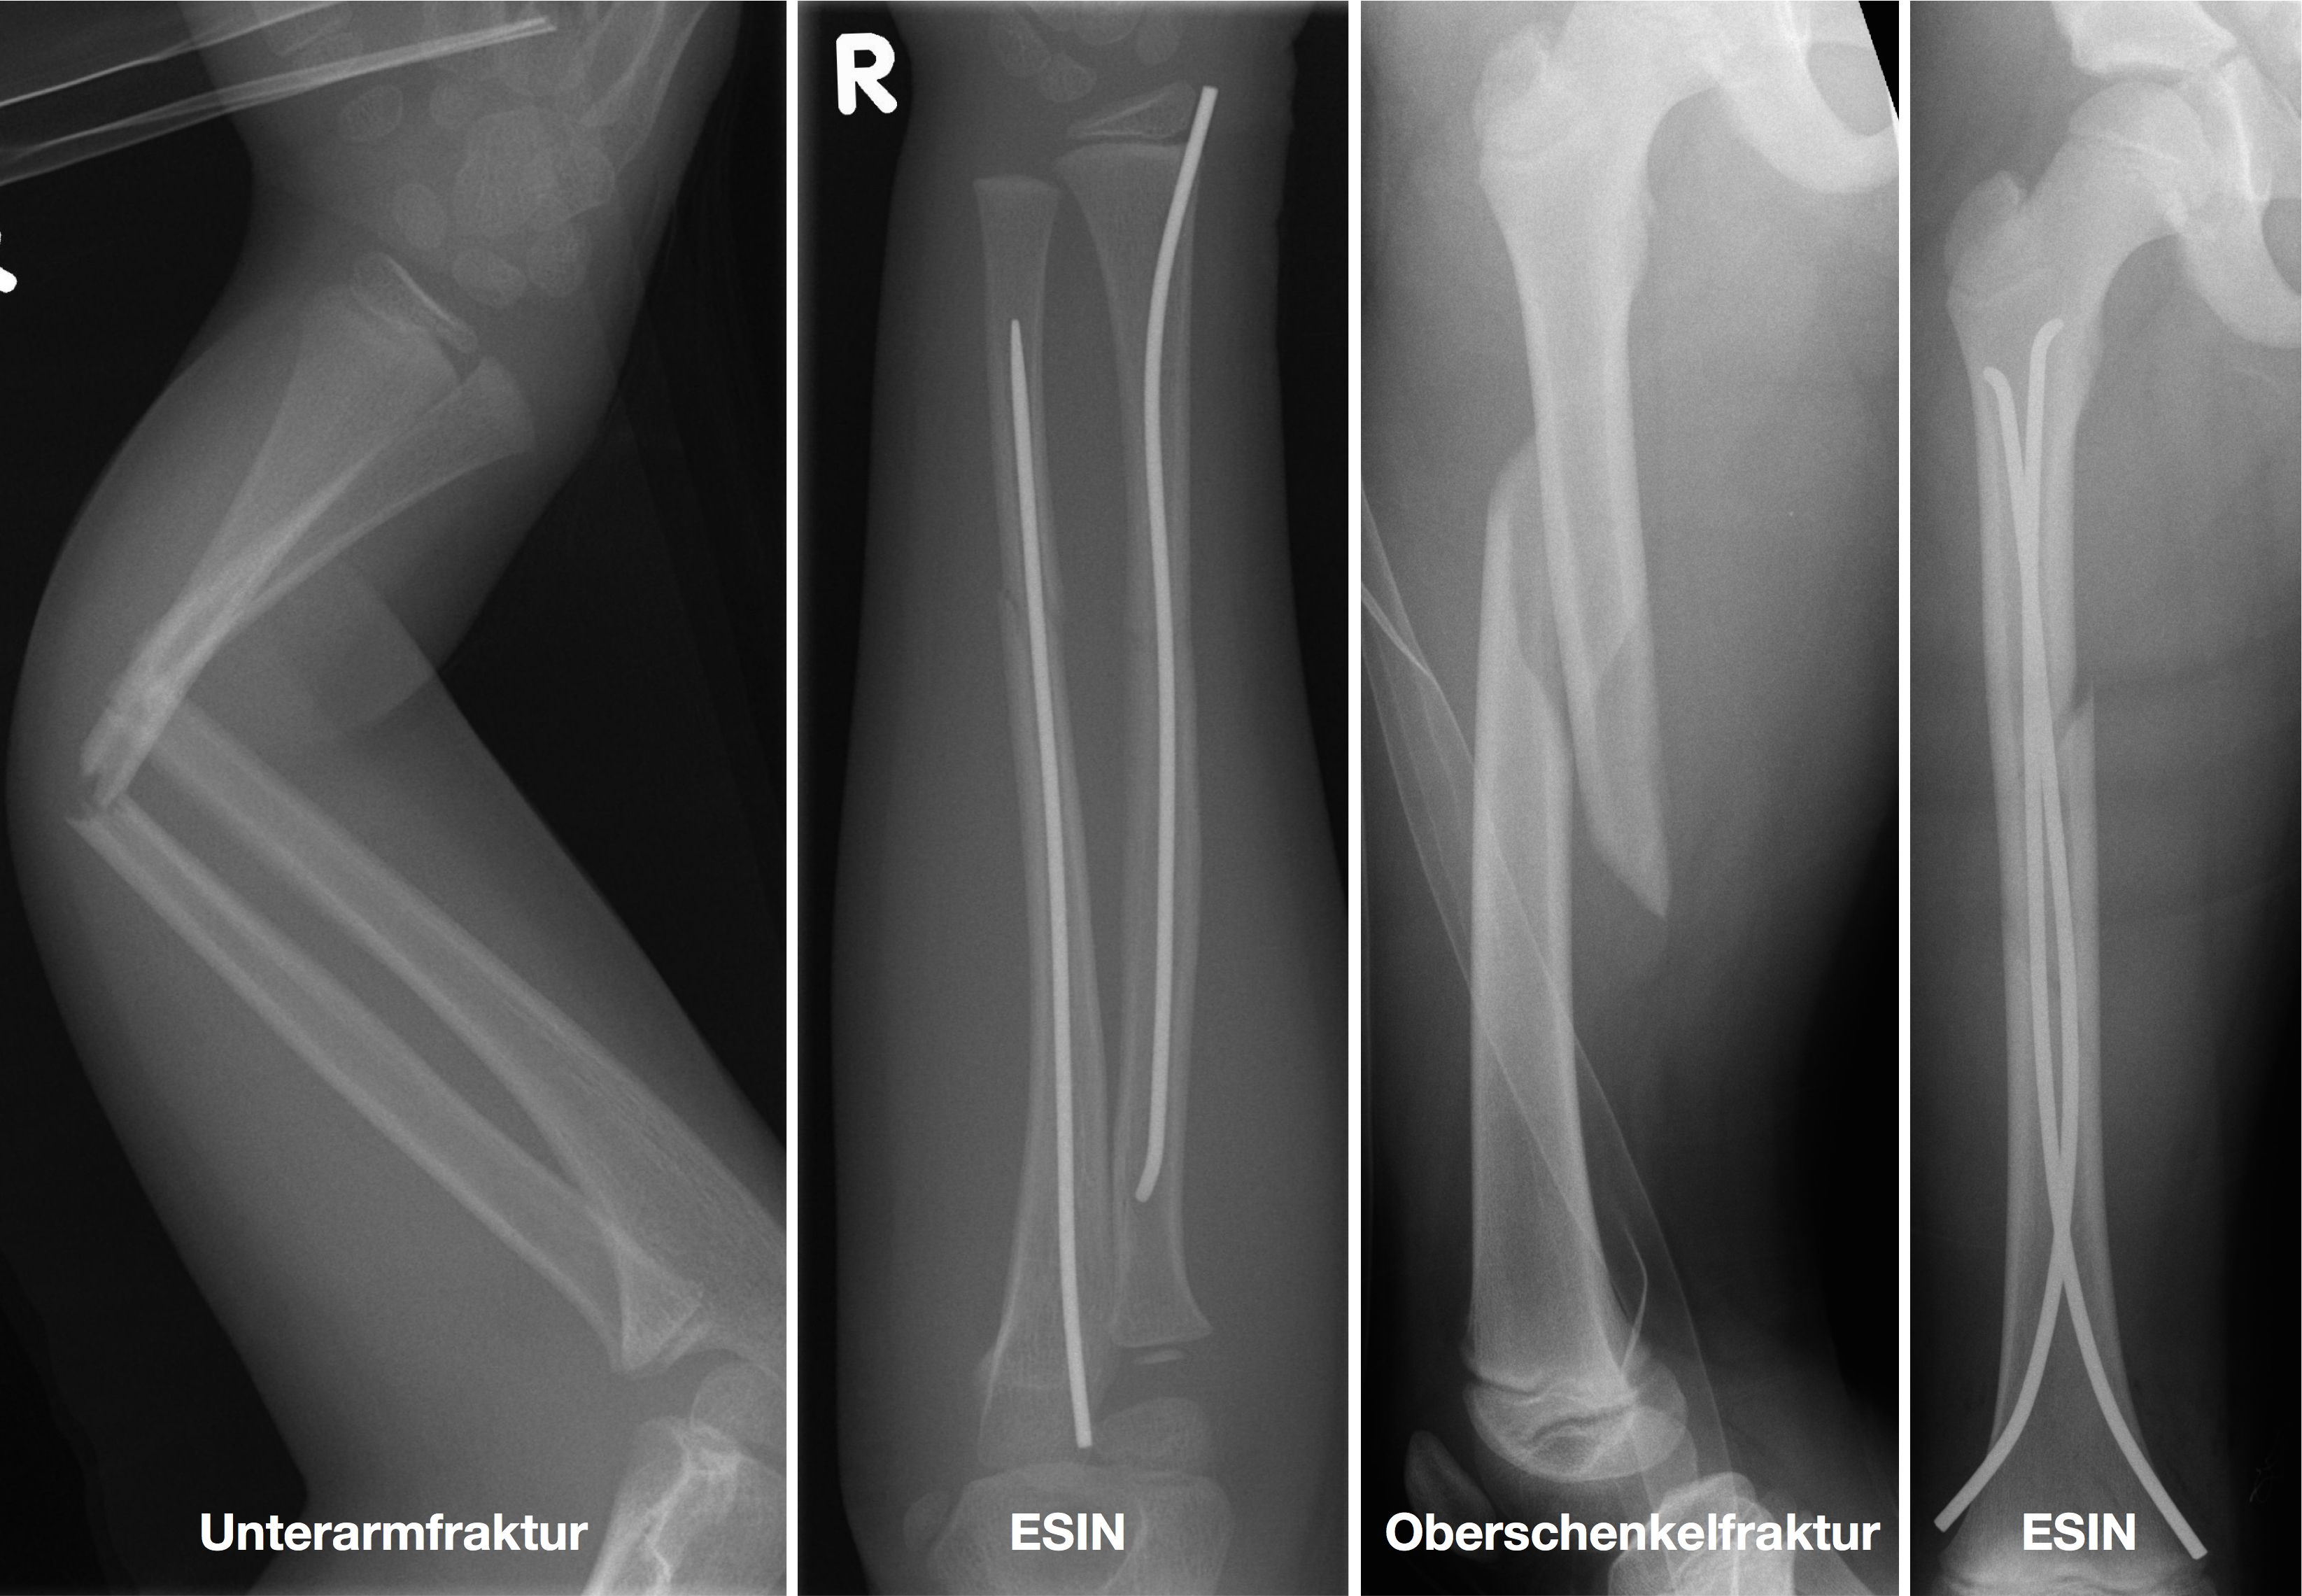

Elastisch stabile intramedulläre Nagelung

Einige Frakturen müssen auf Grund ihrer Achsabweichung operiert werden. In einer Narkose wird die Fraktur eingerichtet und ggf. mit Metall stabilisiert. Dazu stehen eine Reihe von Methoden (Osteosynthesen) zur Verfügung, die speziell für Kinder entwickelt wurden, um Wachstumsfugen zu schonen und nicht zu verletzen: Die ESIN (elastisch stabile intramedulläre Nagelung) hat sich als minimal invasives Standardverfahren zur Stabilisierung von Schaftfrakturen der großen Röhrenknochen (Unterarm, Oberarm, Unterschenkel, Oberschenkel) etabliert. Die Implantate können über winzige Schnitte eingebracht werden, eine gipsfreie Nachbehandlung ist ein weiterer entscheidender Vorteil.

Kirschner-Draht-Osteosynthese

Andere Verfahren der operativen Frakturversorgung im Kindesalter sind die Kirschner-Draht-Osteosynthese, die Verschraubung, der Fixateur und die Plattenosteosynthese. Metallentfernungen werden ambulant durchgeführt, Nachuntersuchungen zum Ausschluss etwaiger Wachstumsstörungen erfolgen in unserer Frakturensprechstunde.